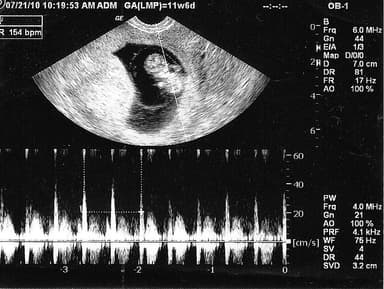

Thai nhi mấy tuần có tim thai? Khoảng 21 ngày sau khi thụ thai, trái tim bắt đầu nhịp đập đầu tiên. Nhịp tim được phát ra từ các sợi cơ tim. Các xung điện di chuyển khắp ống tim nguyên thủy để bắt đầu nhiệm vụ suốt đời đó là duy trì não bộ và các cơ quan quan trọng khác. Trong khi tim bắt đầu đập ở tuần thứ 4-5, các mẹ thường không nghe được nhịp tim thai khi siêu âm, phải đến tuần thứ 9 hoặc 10 mới mới nghe được. Và đến tuần 20, mẹ sẽ nghe được tim thai bằng ống nghe bình thường. Thai máy bao nhiêu lần một ngày

Ở tuần thứ 7, tim thai bắt đầu phân chia thành buồng trái và phải. Bác sĩ có thể nhìn thấy và đo được những điểm sáng nhấp nháy trên máy siêu âm. Ở giai đoạn này, nhịp tim của bé rơi vào khoảng 90-110 nhịp/ phút. Nhịp tim của bé đạt đỉnh cao nhất vào khoảng tuần 9, từ 140-170 nhịp/phút. Các tuần thai sau này, tim của bé sẽ hoàn chỉnh hơn về cấu tạo và chức năng cũng như kích thước. Giai đoạn này, nhịp tim của bé sẽ vào khoảng 120-160 nhịp/ phút.

Nhịp tim bình thường ở tuần thứ 6-7 khoảng 90-110 nhịp/mỗi phút. Ở giai đoạn này, tim thai mới xuất hiện, và sự hiện diện này chính là một dấu hiệu đảm bảo cho sức khỏe của thai kỳ.

Giai đoạn tuần 7, 8, 9, 10: trong suốt khoảng thời gian này, nhịp tim của bé sẽ tăng lên đáng kể. Đây là dấu hiệu cho thấy mọi thứ hoàn toàn bình thường. Ở tuần thứ 6, nhịp tim là 110 nhịp/phút, sau đó nó sẽ tăng trong tuần thứ 7 và đạt mức 170 nhịp/phút ở tuần 9-10. Nhịp tim này tiếp tục duy trì trong 4 tuần tới.